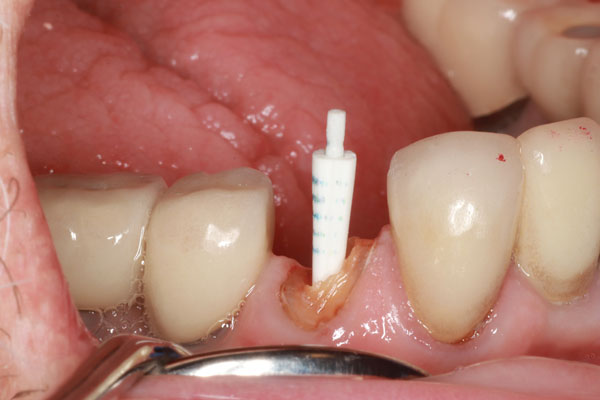

Un paciente se presentó con un diente roto (es decir, el diente No. 28) que requirió tratamiento de conducto. Hubo una pérdida significativa de estructura dental; por lo tanto, se consideró necesario un tratamiento posterior y central para sostener una corona (Figura 1). El paciente fue anestesiado y se excavó cualquier caries restante. Después de obtener, evaluar y medir una radiografía, se utilizó un taladro para eliminar aproximadamente dos tercios de la longitud del material de obturación del conducto radicular (Figura 2). Se tomó otra radiografía para confirmar que la profundidad alcanzada era correcta. A continuación, se probó primero el sistema de poste ajustable único (Splendor SAP, Angelus) sin el manguito para determinar si estaba completamente asentado (Figura 3). Luego se probó con el manguito y se consideró que encajaba bien (Figura 4).

Imagen 2 Se utilizó un taladro para retirar el material de relleno endodóntico a la profundidad ideal.